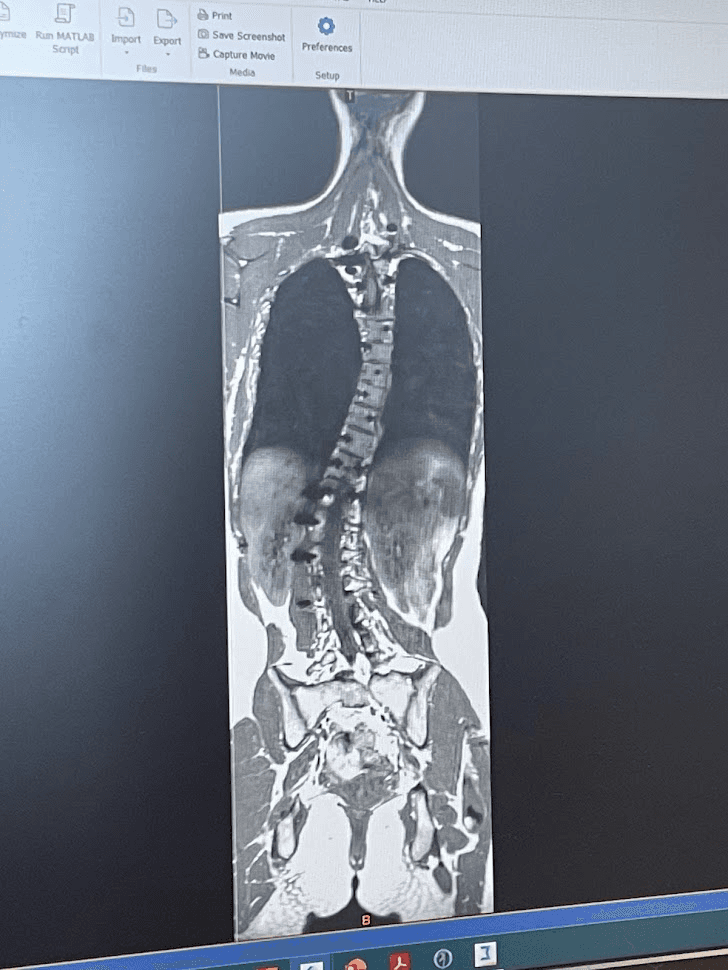

My MRI scan for the other

spine Ph.D.'s project optimization!

07/19/24

Leuven